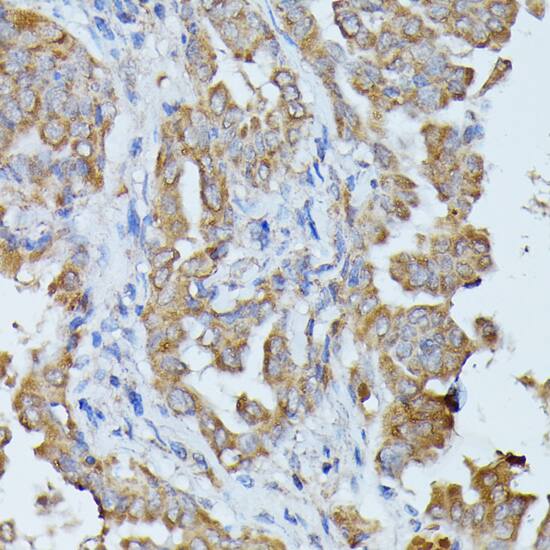

Immunohistochemistry: Histidase Antibody [NBP3-35300] -

Immunohistochemistry: Histidase Antibody [NBP3-35300] - Immunohistochemistry analysis of paraffin-embedded Human thyroid cancer using Histidase Rabbit pAb at dilution of 1:100 (40x lens). Microwave antigen retrieval performed with 0.01M PBS Buffer (pH 7.2) prior to IHC staining.